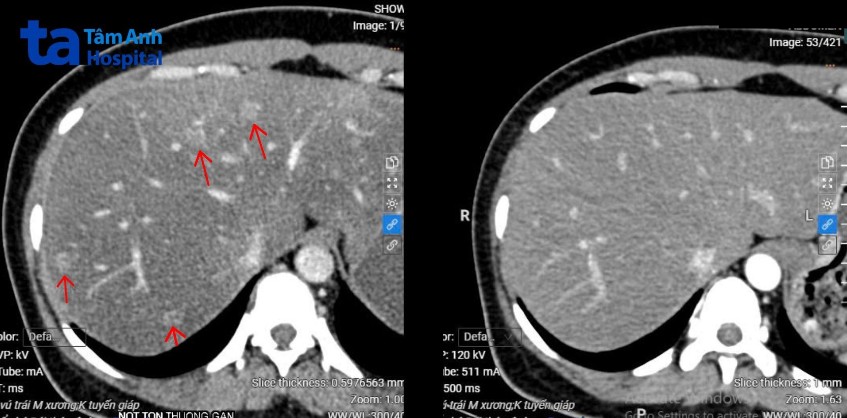

Sau ba năm, kiểm tra cho thấy khối u vú của chị Phương không còn, các nốt di căn gan tiêu biến, tổn thương xương đặc hóa, không gây đau. Suốt quá trình điều trị, chị không gặp tác dụng phụ đáng kể, không rụng tóc hay buồn nôn mà ăn uống ngon miệng, sinh hoạt bình thường. Hiện, chị Phương tiếp tục được tái khám định kỳ và điều trị duy trì.